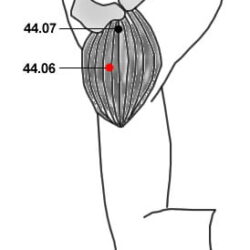

אזור DT

DT.01 – מפריד ענף עליון Fēn Zhī Shàng 分枝上 DT.02 – מפריד ענף תחתון Fēn Zhī Xià 分枝下 DT.03 – שבעת הכוכבים Qī Xīng七星 DT.05 – שני עוף החול Shuāng Fèng 雙鳳 DT.08 – ענף התמצית Jīng Zhī 精枝 DT.09 – יער המתכת Jīn Lín 金林 DT.15 – שלושת הנהרות Sān Jiāng 三江 DT.17 – לשגר מעלה לשמיים Chōng Xiāo 衝霄